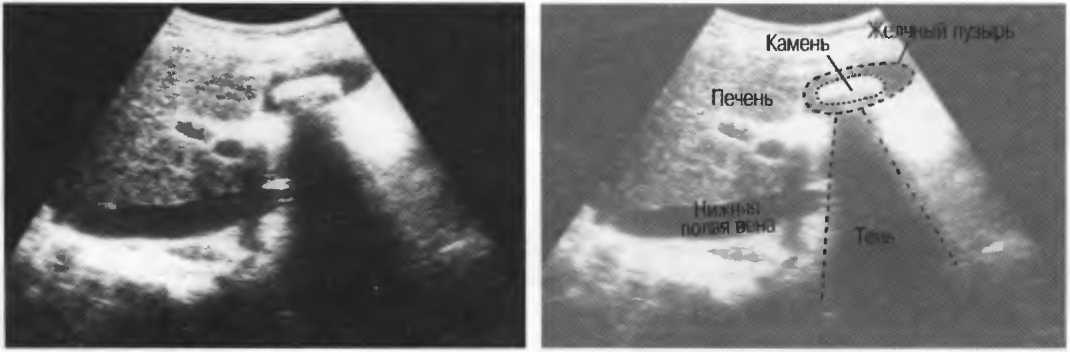

Плотные материалы, такие как кости или камни, дают акустическую тень на структуры, расположенные сзади, в результате того что ультразвуковая волна не проходит через них. Этот феномен получил название «акустической тени». Например, ребра могут экранировать ультразвуковой поток, поэтому структуры, расположенные за ними, нужно исследовать в косом направлении по межреберным промежуткам (рис. 10б,в).

Тени

Кости, камни и кальцинаты дают акустическую тень. Ультразвук не может проходить через кость, если она только не очень тонкая (как, например, кости черепа у новорожденного). При необходимости рассмотреть структуры, расположенные глубже, необходимо использовать различные углы наклона датчика (рис. 17а,б).

Рис. 17а. Большая акустическая тень за камнем в желчном пузыре.

Рис. 176. Это изображение почки частично экранировано тенью ребра. Сканирование в различные фазы дыхания поможет визуализировать всю почку целиком, «вывести» ее из-под ребра.